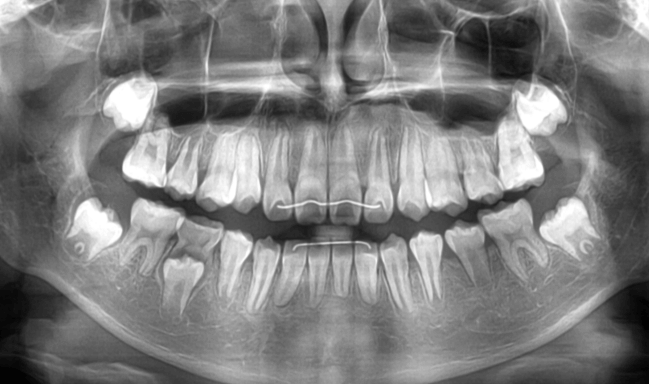

| 年齢・性別 | 8歳3ヶ月の男児 |

|---|---|

| 主訴 | 上顎前歯の位置異常に不安を抱え、歯並びと将来的な咬合状態を整える目的で来院された患者様です。 特に左側の前歯(中切歯および側切歯)の萌出が確認できないことがきっかけとなりました。 |

| 治療期間・回数 | 約5年10ヶ月 |

| 費用 | 460,000円(税別) |